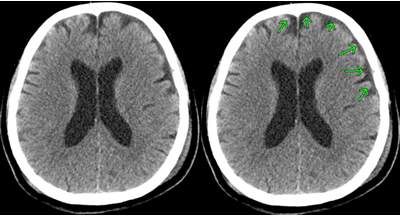

⑧ 急性硬膜下血腫

【CT画像】

【MRI画像】

画像は巨大な三日月型の急性硬膜下血腫です。

急性硬膜下血腫は、頭蓋骨のすぐ内側で脳を覆っている硬膜と脳の間に出血がたまって血腫となったものです。交通事故外傷でよくある傷病名です。

脳挫傷や脳表の小さな血管による出血が脳の表面と硬膜の間に流れ込み、短時間のうちにゼリー状に固まり脳を圧迫します。これが急性硬膜下血腫となります。

血腫による圧迫と脳挫傷のために頭蓋内圧力が亢進すると、激しい頭痛、嘔吐、意識障害などが生じます。血腫による圧迫によって脳ヘルニア状態にまで進行し、深部にある脳幹が侵されて呼吸障害などを生じるようになると、最悪の場合には死に至ります。

受傷当初は意識障害がない例でも、一旦意識障害が発現するとその後は急激に悪化することが多く、予後はきわめて不良です。

血種の外科手術後も脳挫傷が伴うときは、後遺障害となることが多いです。